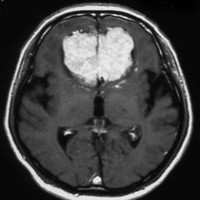

上矢状洞髄膜腫 superior sagittal sinus meningioma

上矢状洞を埋め尽くすように増大して,頭蓋骨浸潤が著しい髄膜腫ですが,ごく軽度の右足脱力以外に何の症状もありません。上矢状洞はゆっくり閉塞すれば,このような頭頂部から後頭部にわたる広範閉塞でも,静脈還流に障害がない場合が多いといえます。大脳の前半部の血流は前頭葉表面の皮質静脈から海綿静脈洞に側副路を形成しています。頭蓋内圧亢進所見もなく,これらはこの髄膜腫がゆっくり増大したということを示唆しています。

手術直後の画像です。全部いっぺんに摘出するのは無理なので,まず前から80%くらいの腫瘍を摘出しました。肥厚した骨はチタンプレートで置き換えてあります。後頭部の上矢状洞内と大脳鎌に少し残りましたが,この6ヶ月後に2回目の開頭術をして全摘出しました。結果的にこの例では,上矢状洞を冠状縫合のあたりから,静脈洞交会まで壁ごと全部摘出しましたが,脳浮腫も何も生じませんでした。腫瘍の両側にある皮質静脈 cortical veinsを損傷しないことが肝要です。